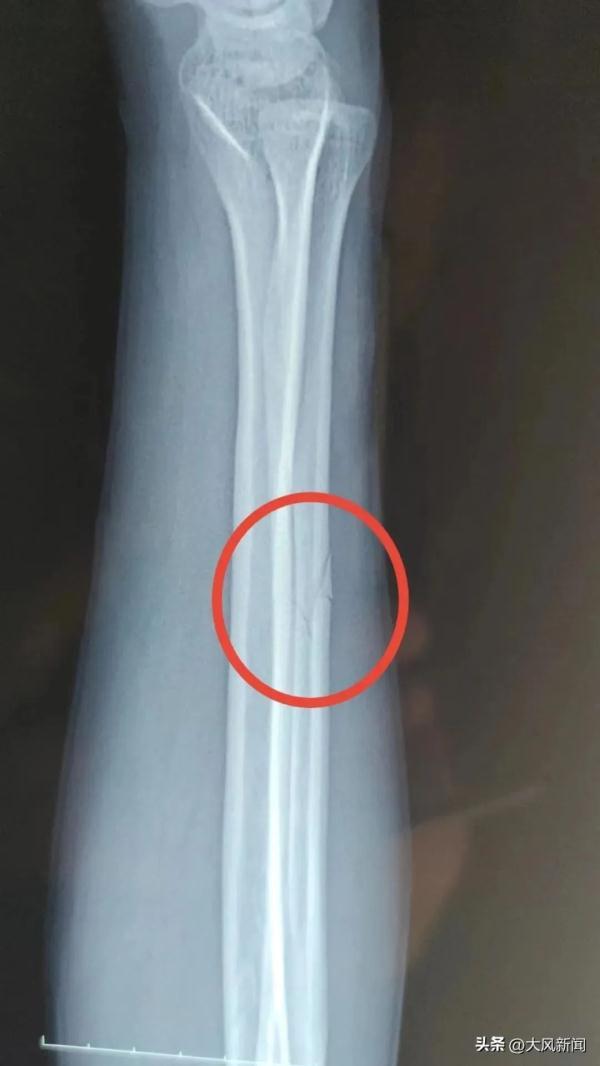

事發后宋某報了警,當晚去醫院檢查并打了石膏,醫生讓先回家觀察。宋某系第二天右臂痛疼難忍,于2022年11月13日下午6時自行前往丹鳳縣醫院檢查。經診斷右尺骨骨折,外傷性頭疼。

宋某家屬并不認可“輕傷二級”的鑒定結果,申請重新鑒定。4月18日宋某拿到了鑒定意見通知書。宋某人體損傷程度屬于輕傷一級。